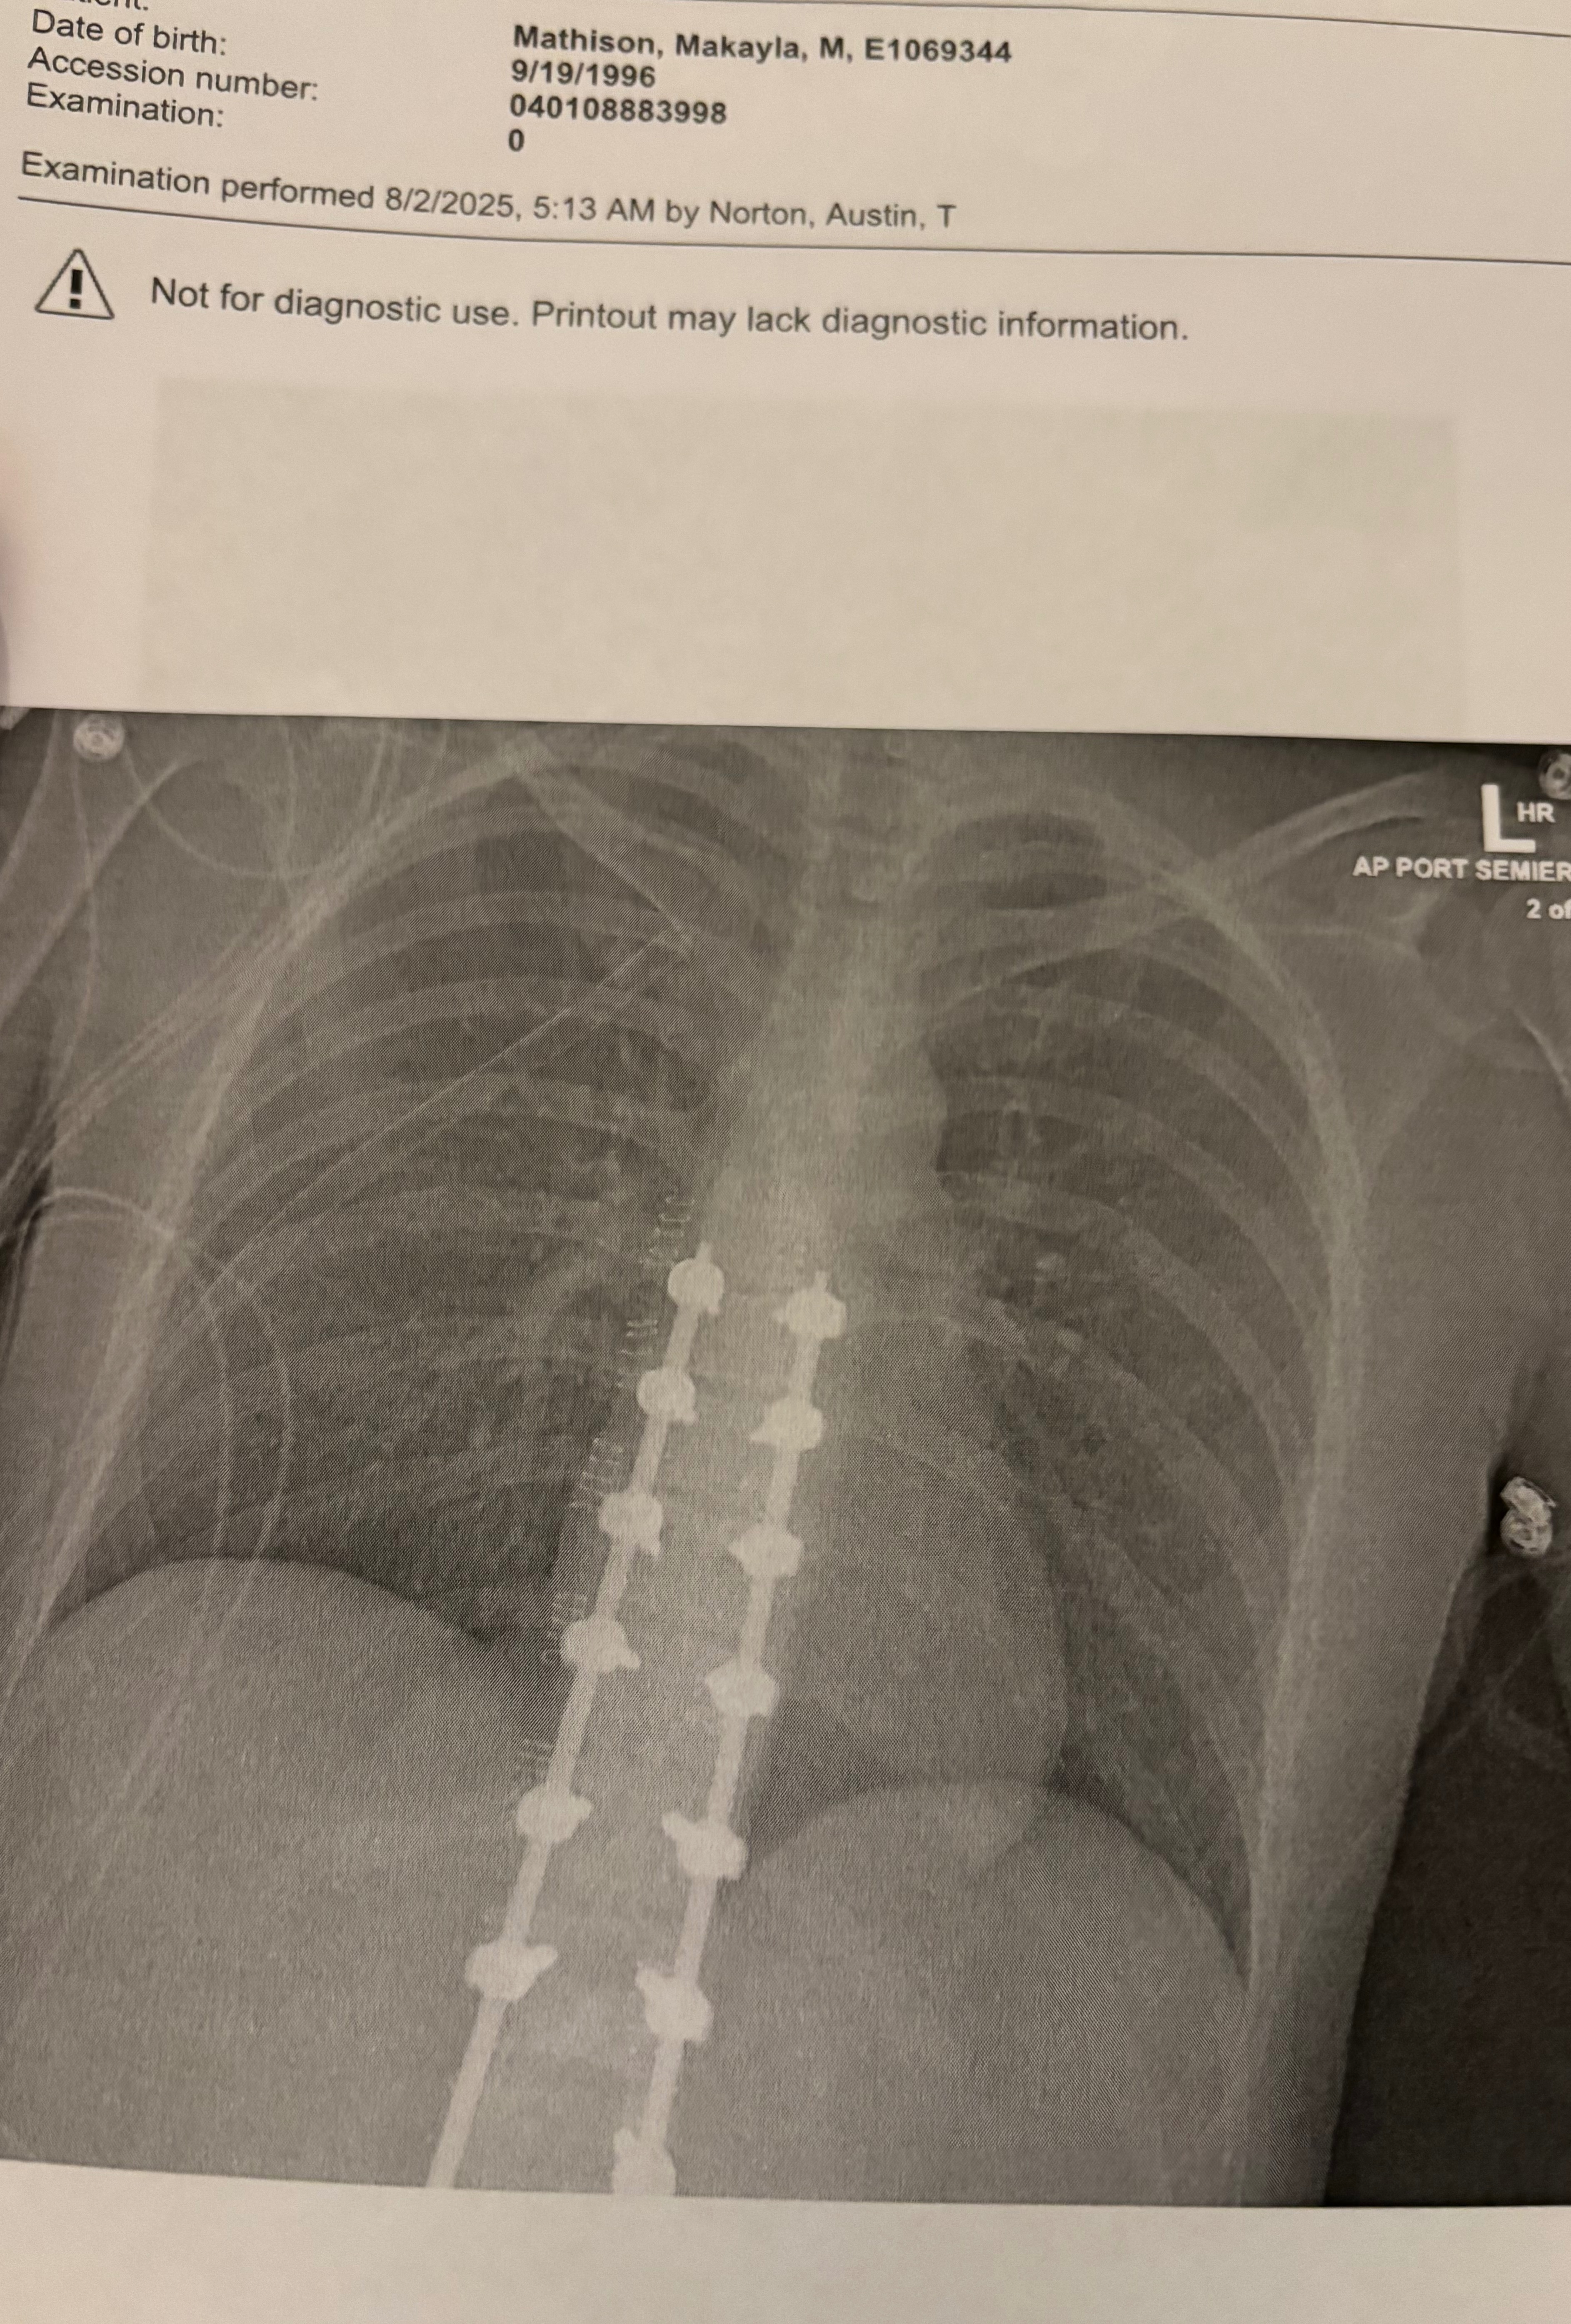

I was rushed to the hospital in Sisseton, SD, and immediately life-flighted to Fargo, ND, where I underwent emergency surgeries. The injuries were catastrophic. I had broken my L2 and T10 vertebrae and torn my dermal cord, which caused spinal fluid to leak dangerously. Doctors had to place a drain in my back, perform spinal fusion surgery, and insert rods to stabilize my spine & leaving me with 122 staples down my back.

That wasn’t all. My left hip and femur was broken. My sternum was fractured. A large portion of my ribs were shattered. One of my lungs collapsed and had to be partially removed. A chest tube was inserted just so I could breathe.